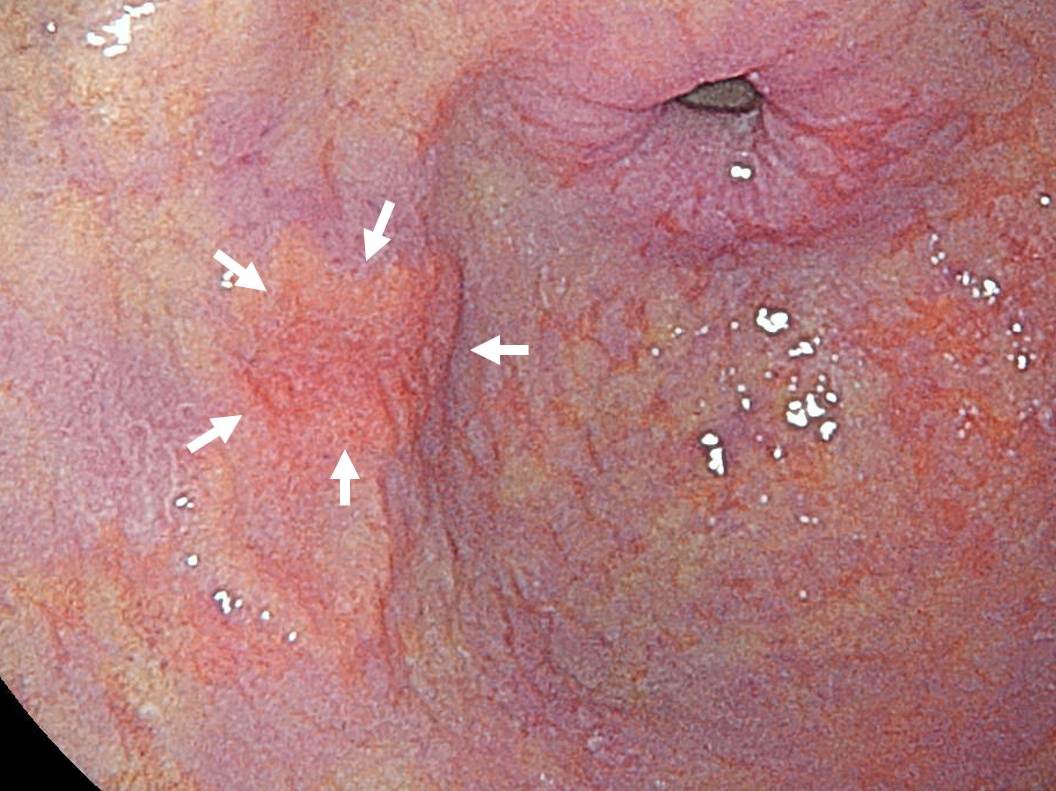

- 胃内視鏡検査:レーザーの光を用いており、早期胃癌を発見しやすくなりました。